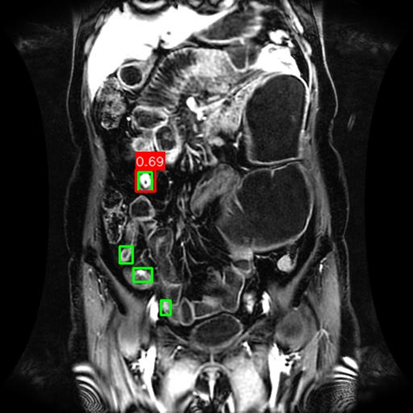

(a) Mask R-CNN [He2017MaskRCNN]

Refer to caption

(b) DiffusionDet [Chen2023DiffusionDet_ICCV]

(c) DeFloMat (Ours)

Figure 3: Qualitative Comparison on Crohn’s Disease MRE Test Set. The figure compares detection results from (a) Mask R-CNN, (b) DiffusionDet (S=3S=3), and (c) DeFloMat (Ours, S=3S=3) on challenging MRE slices. Green boxes indicate True Positives (TP, IoU 0.1\geq 0.1), Red boxes indicate False Positives (FP), and Purple boxes indicate False Negatives (FN). DeFloMat consistently demonstrates superior localization quality and sensitivity: it successfully detects subtle inflammation regions (TP) that are often missed (FN, Purple boxes) by the Mask R-CNN baseline (Row 2, 4). Furthermore, DeFloMat provides tighter bounding box localization compared to DiffusionDet, confirming the benefit of learning the direct, deterministic flow field. The results show DeFloMat’s robustness in capturing varying sizes and numbers of inflammatory lesions.

Qualitative Assessment.

Figure 3 provides visual evidence of the models’ performance on challenging MRE slices, where inflammatory lesions can be subtle or obscured. The qualitative results underscore DeFloMat’s enhanced localization fidelity. In challenging cases (e.g., Row 2 and 4), Mask R-CNN and DiffusionDet frequently produce False Negatives (FN, Purple boxes), failing to detect clear inflammation sites. In contrast, DeFloMat reliably converts these FNs into True Positives (TP, Green boxes) by providing tighter and more accurate bounding box predictions. This suggests that the deterministic velocity field learned via Flow Matching is highly effective at precisely directing the proposal centers towards the true lesion locations, a characteristic that is vital for accurate clinical reporting. DeFloMat’s ability to achieve such precise localization with only S=3S=3 steps highlights its clinical utility for rapid diagnostic auxiliary systems.